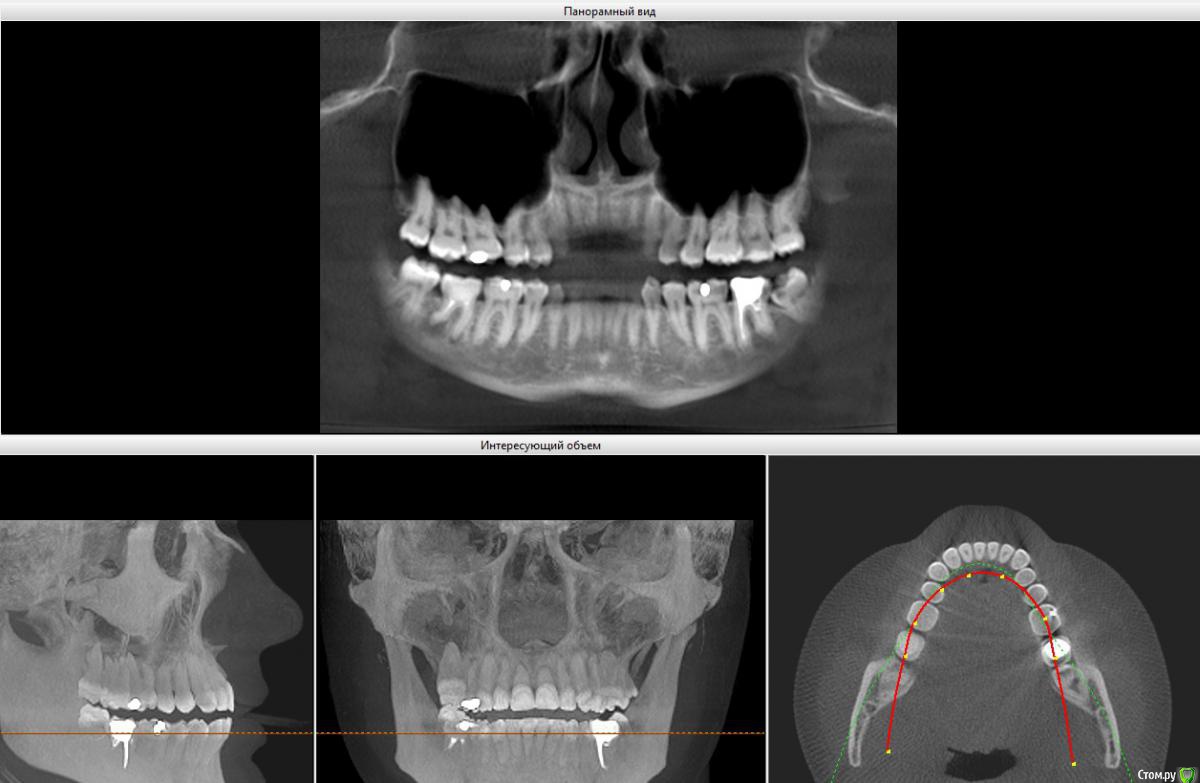

Вердикт ортодонта - имеется легкая скученность спереди, удалить обе 8ки на НЧ, на 7ку керамическая коронка и ровнять брекетами.

Вопрос 2. Если ставить брекеты. Только снизу или на обе челюсти? И как тогда быть с зубами мудрости наверху? С одной стороны у меня их девять :blink: (картинка 5, обведено красным кругом).

2. 1 или 2 челюсти решает врач. чаще всего две.  Зубов у Вас ровно столько , сколько должно быть  (в красном кружочке наложение верхней и нижней челюстей)

если удаляете что-то внизу, то и верхние надо  будет (иначе они начнут опускаться вниз, будет блок)

3. предложение стоматолога реально, тем более учитывая, что 7-ки совсем не ах. Только нужно очень захотеть и постараться.